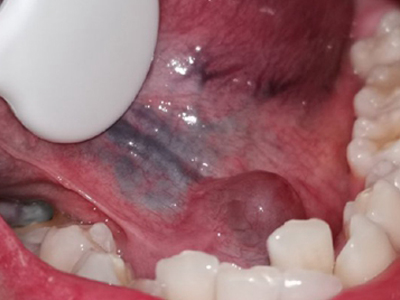

舌下腺囊肿舌头下面长了一个圆形肿块图

舌下腺囊肿位于舌底一侧,表现为圆形、光滑、柔软的肿块,直径约3cm大小,紧贴下牙,囊肿壁薄,呈浅紫蓝色,破裂并流出黏稠的液体。